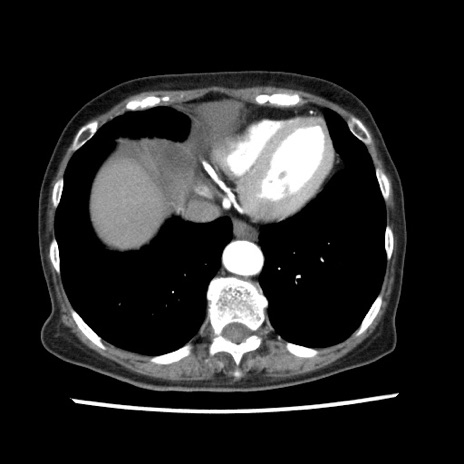

症例1(横断像)

【症例】80歳代女性

【主訴】腹痛

【現病歴】8時間前から腹痛あり来院。

【既往歴】糖尿病、脂質異常症、子宮体癌にて子宮全摘術

【身体所見】意識清明・会話良好だが腹痛で苦悶様、全腹部にわたって反跳痛と圧痛あり

【データ】WBC 13600、CRP 0.14、LDH 224、CK 90